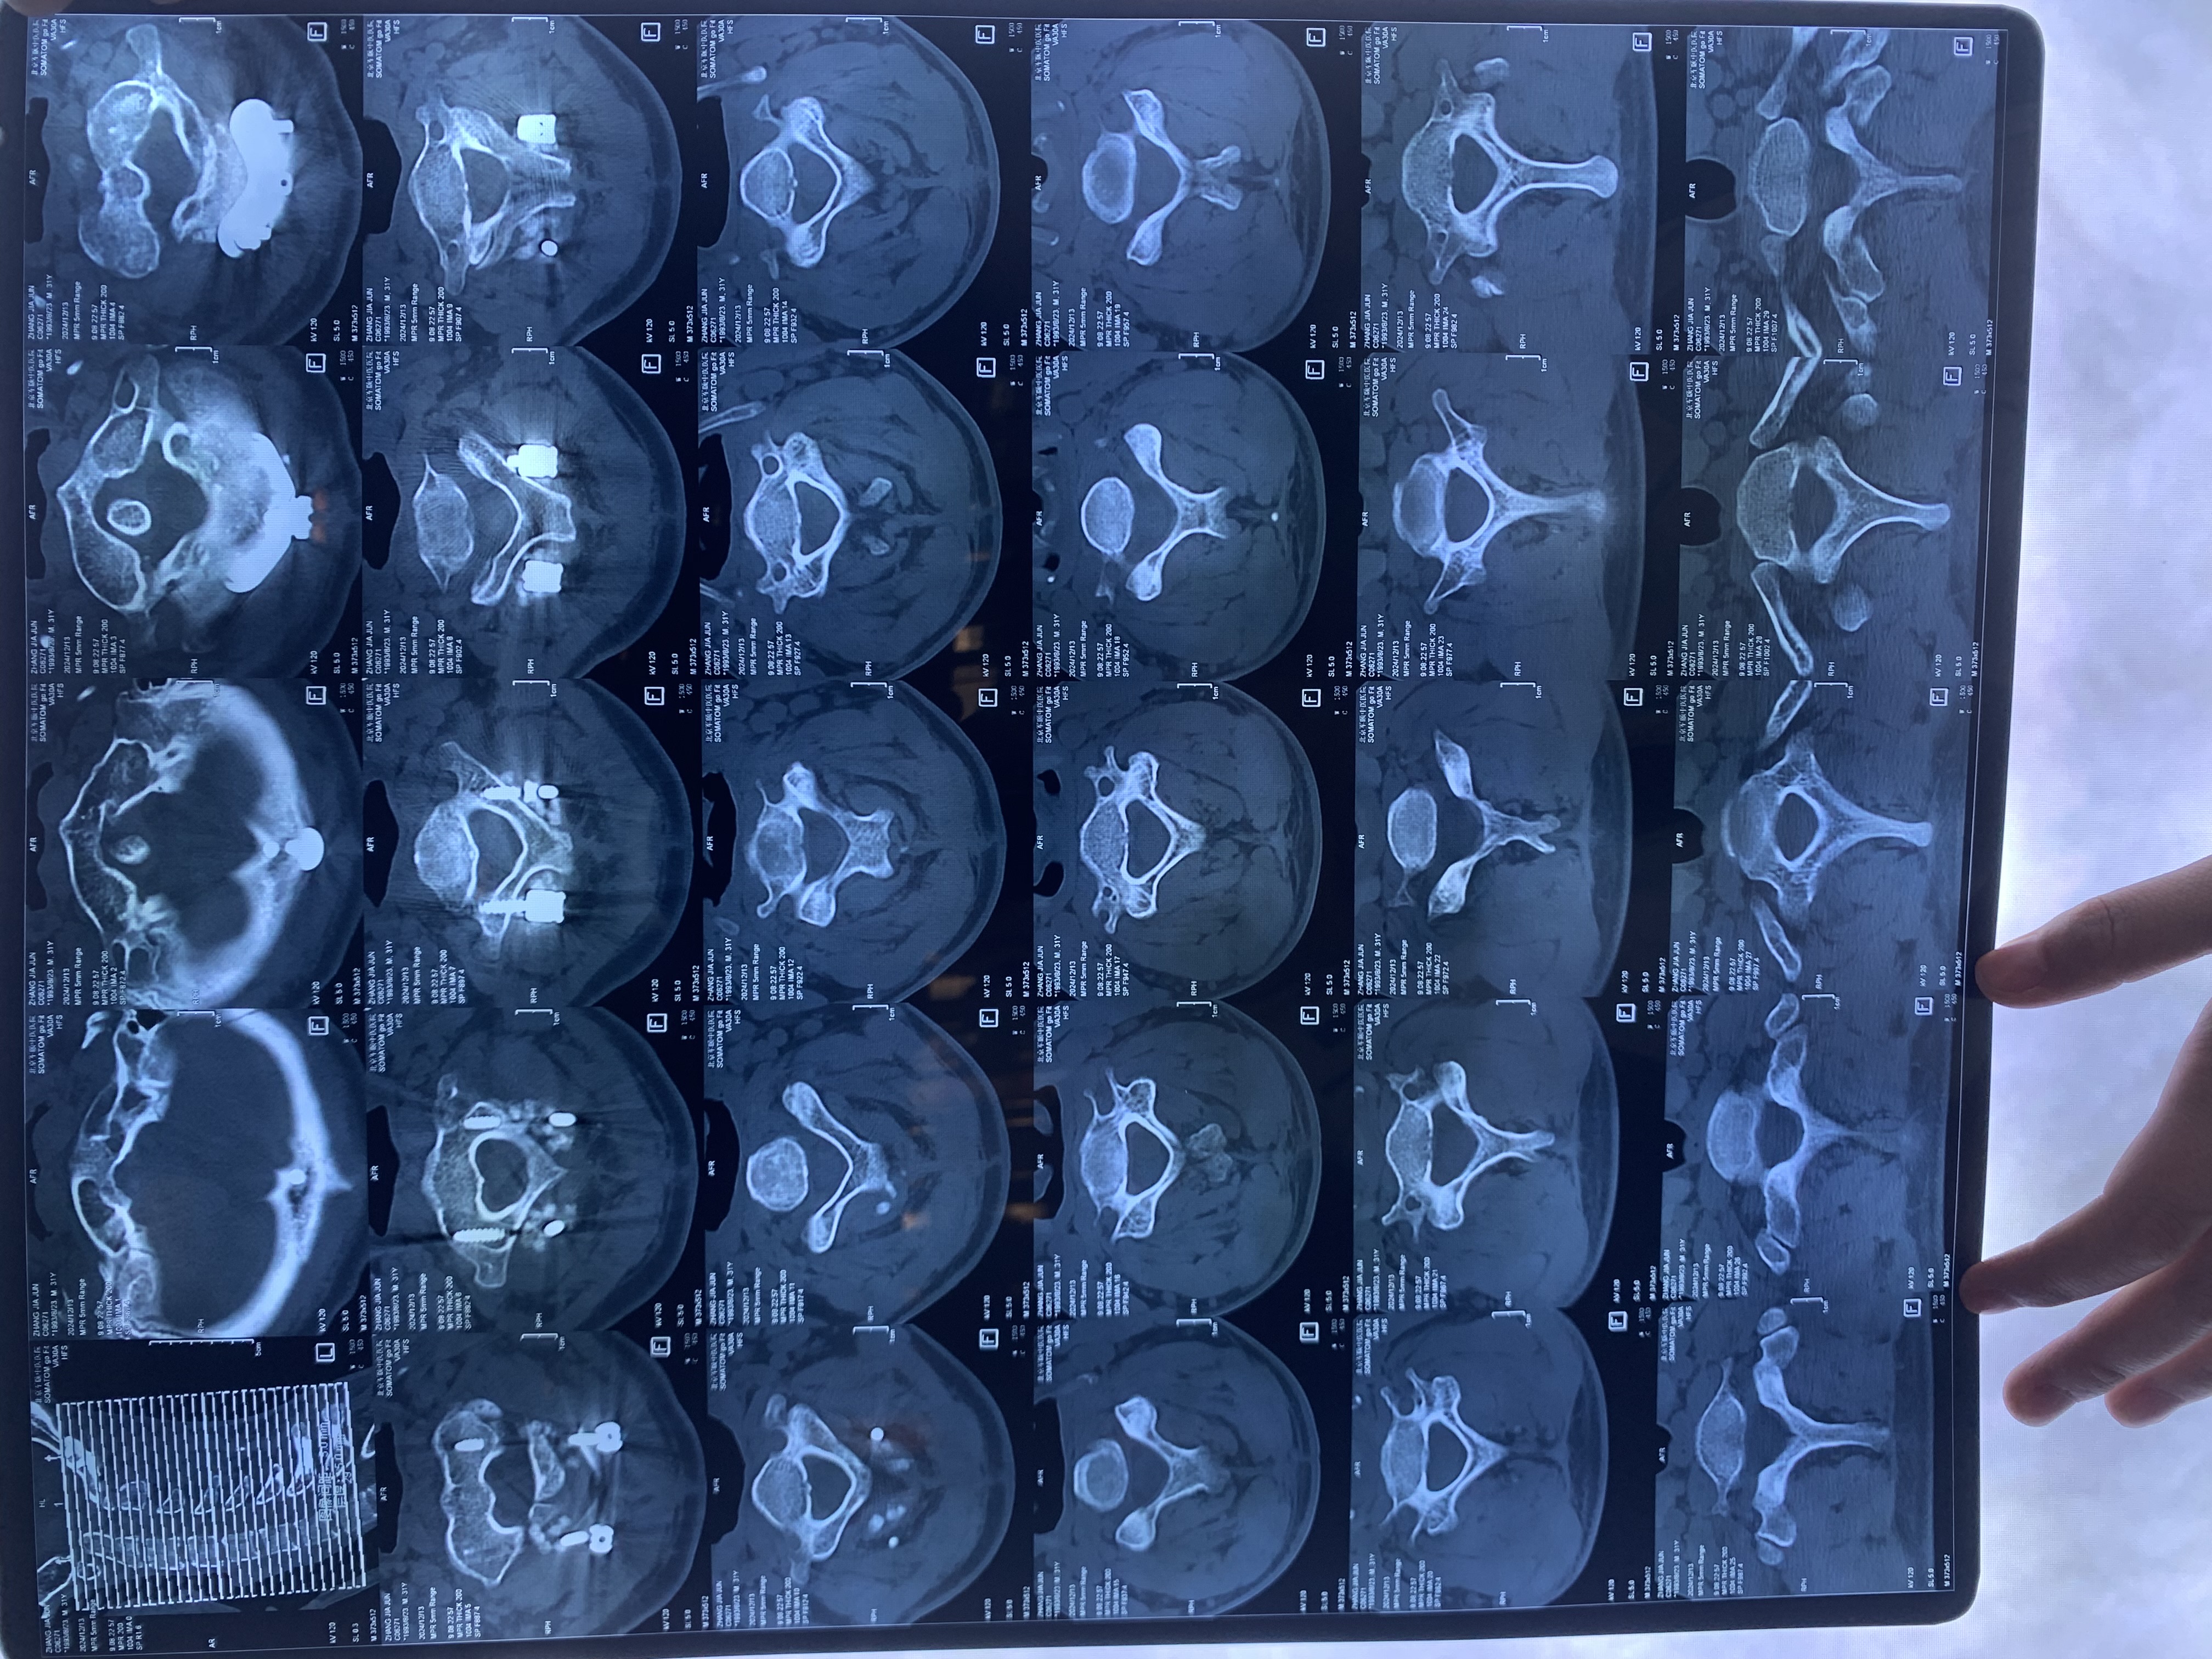

• 术后状况:头晕症状还在,但握拳有劲了,第二天看ct片子,寰齿间隙还是大于3mm,颅底凹陷没有任何改善。

• 术后影像:

• 2024.12.13,去北京拍片,当天走路有点多,感觉脑袋里面疼。影像报告脱位和颅底凹陷都还在,影像如下: